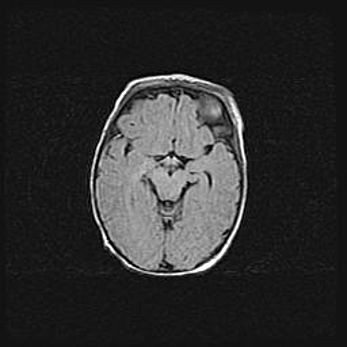

Открытая гидроцефалия.

Возраст: 9 месяцев 12 дней

Вес: 6800 г

Пол: мужской

Окружность головы: 41,5 см

Срок гестации: 28 недель

Гидроцефалия головного мозга у новорожденных имеет характерный признак: опережающий рост окружности головы приводит к визуально хорошо определяемой гидроцефальной форме сильно увеличенного в объёме черепа. Детские неврологи определяют следующие симптомы гидроцефалии у грудничков: выбухающий напряжённый родничок, частое запрокидывание головы, смещение глазных яблок к низу.